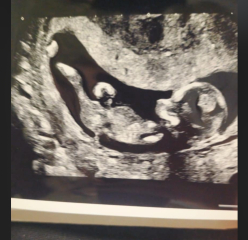

Natalie303 · 07/11/2024 19:24

What does everyone think?

boy or girl. 12 weeks scan.